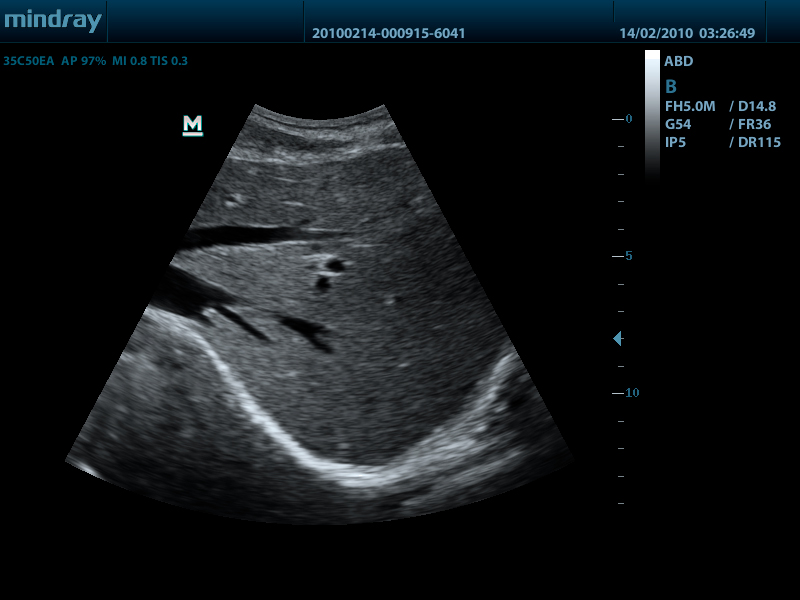

Конвексный датчик 35C50EA (2.0/3.5/4.5/5.0/Н5.0/Н6.0) R50